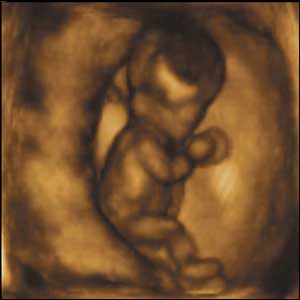

8 týdnů, 40 mm

V osmi týdnech života je plod schopný kopat a natahovat nohy, točit s nimi a zvedat ruce nahoru a dolů.